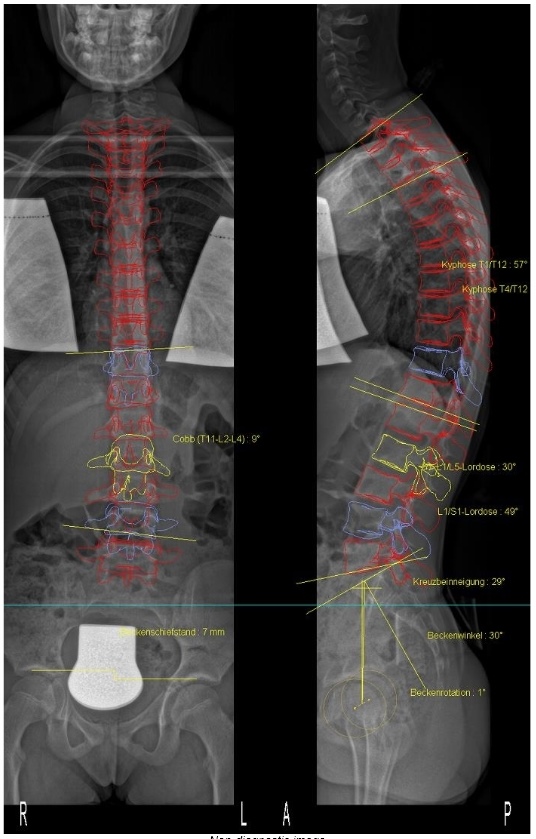

Zu meinem Becken: von Dr. Hoffmann wurden mir nach an die 10 3D-Aufnahmen mit unterschiedlichem Höhenausgleich eine Einlage von 0,9cm verschrieben. Das EOS sieht aber keinen Beckenschiefstand (bzw. nur 1 mm). Also keine Schuherhöhung. Das entspricht nun auch viel mehr meinem eigenen Körpergefühl. Die Einlage hatte ich eigenmächtig nach ein paar Wochen wieder weggelassen.

Der Termin bei Herrn Vogel ging recht schnell. Nach einem kurzen Gespräch wurde ich vermessen und fotografiert. Laut seiner Aussage bekomme ich (wahrscheinlich) ein kurzes Korsett. Ich laufe unter Lumbalskoliose. Die thorakale Krümmung könne man, da kaum Rotation, quasi vernachlässigen.

Diese Aussage konnte ich erstmal gar nicht annehmen, denn seit meiner Skoliose-Karriere auch in beiden Rehas hieß meine Skoliose IMMER thorakolumbal 4bogig und ich musste auch im thorakalen Bereich immer asymmetrisch arbeiten (z.B. Schultergegenzug). Laut Herrn Vogel sei das die ganzen Jahre aber FALSCH gewesen!